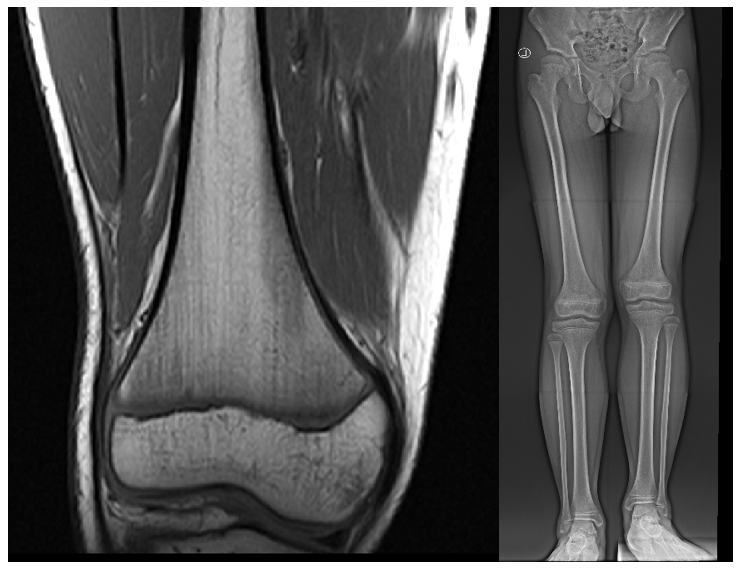

我院骨病诊疗中心李刚博士,采用数字骨科技术通过医工结合的方式,为儿童股骨远端内外侧骨骺固定术患者,依据患者磁共振数据进行高精度的三维图像构建,精准的术前规划、个性化穿针固定导板设计,为10例患者成功实施微创手术治疗,取得了满意效果。

核磁共振可避免射线对儿童健康的影响,且MR图像能清晰显示股骨远端内外侧骨骺的解剖结构、病变范围及周围软组织情况,但三维成像难度较大。医工结合团队多次讨论,共同参与设计三维图像结构,并模拟手术治疗固定点的位置、角度和深度等,并根据三维成像设计个性化手术固定导板,利用3D打印技术个性定制,术中精准引导手术操作,使手术过程更加高效。术中,通过小切口进行微创精准操作,相比传统开放手术,减少了对周围组织的损伤,减少了手术时间和术中出血,避免了神经血管损伤风险,降低了术后感染、瘢痕形成等并发症。